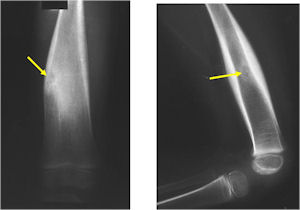

Plain X-Rays:

- Lucent nidus surrounded by a zone of marked sclerosis

- The nidus may demonstrate mineralization/ossification usually from the center outward that appears as a central zone of density within the nidus

- A nidus that is heavily ossified may blend in with the surrounding sclerosis and be difficult to detect on a plain x-ray.

- Periosteal bone is solid, rarely lamellated

- Cortical and subperiosteal osteoid osteomas are usually associated with much more reactive sclerosis than medullary tumors

- The periosteal reaction is continuous and often appears as cortical thickening (benign appearing reaction)

- Intracapsular osteoid osteomas are difficult to identify because there is no periosteum in the intracapsular region and hence a periosteal reaction does not occur.